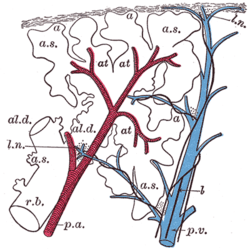

Diagram of the alveoli with both cross-section and external view. | |

A pulmonary lobule is the portion of the lung ventilated by one bronchiole. Bronchioles are approximately 1mm or less in diameter and their walls consist of ciliated cuboidal epithelium and a layer of smooth muscle. Bronchioles divide into even smaller bronchioles, called terminal, which are 0.5mm or less in diameter. Terminal bronchioles in turn divide into smaller respiratory bronchioles which divide into alveolar ducts. Terminal bronchioles mark the end of the conducting division of air flow in the respiratory system while respiratory bronchioles are the beginning of the respiratory division where actual gas exchange takes place.

The respiratory bronchioles are the narrowest airways of the lungs, one fiftieth of an inch across.[1] The bronchi divide many times before evolving into the bronchioles. The bronchioles deliver air to the exchange surfaces of the lungs.[2] They are interrupted by alveoli which are thin walled evaginations. Alveolar ducts are distal continuations of the respiratory bronchioles.